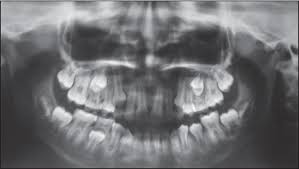

What Does Bone Cancer In The Mouth Look Like : Visual Guide To Bone Cancer / People with a fracture next to or through a bone tumor usually describe sudden severe pain in a bone that had been sore for a few months.. As you review these images and their descriptions, you. It is important that all these symptoms are identified at an early stage so, to give timely treatment. These cancers usually occur in the thin, flat cells called squamous cells that line the buccal mucosa and other parts of the mouth. Cancer in the jaw often spreads there from other areas of the mouth or throat. Oral cancer in dogs is the fourth most common canine cancer and accounts for about 6% of all tumors.

Cancer that arises from the jaw bone is termed primary jaw cancer. If a tumor spreads to the bone, it's called bone metastasis. Some of the most common oral cancer symptoms and signs include: Inner cheek cancer (also called buccal mucosa cancer) is a type of head and neck cancer that begins when the cells that make up the inner cheek grow out of control and form lesions or tumors. Symptoms are similar to more typical osteosarcomas except that they may occur in very young children and are more widespread.

Visual Guide To Bone Cancer from img.webmd.com Cancer in the jaw often spreads there from other areas of the mouth or throat. A white or red patch on the gums, tongue, tonsil, or lining of the mouth. Gingiva cancer (also known as squamous cell carcinoma) is a progressive, rapid (weeks) local invasion of neoplastic epithelial cells within the oral cavity of dogs. A lump or thickening in the cheek. A sore throat or persistent feeling that something is caught in the throat. It is important that all these symptoms are identified at an early stage so, to give timely treatment. Often, by the time a patient sees a doctor for a diagnosis, the tumor has grown into the neck. If cancer develops, a person may notice:

Taken by mouth or injection, they attack any cancer cells in the body. Although many jaw growths are benign, they can still do plenty of harm. Usually it's spotted first by your dentist, so keeping regular dental exams can help with early detection. Hard palate cancer begins in the bony part on the roof of the mouth. Learn the signs of jaw cancer here. Other symptoms of floor of mouth cancer may include: When cancer spreads to the bones. Most cancer of the palate is squamous cell. Cancer in the bones of the spine can press on nerves, causing numbness and tingling or even. Cancer that has started in one place can spread to and invade other parts of the body. This page looks at the symptoms, causes, and conventional treatment of mouth cancer in dogs. As you review these images and their descriptions, you. Inner cheek cancer (also called buccal mucosa cancer) is a type of head and neck cancer that begins when the cells that make up the inner cheek grow out of control and form lesions or tumors.

Metastases To The Mouth And Jaws A Contemporary Canadian Experience Jcda from jcda.ca This is known as a smoker's patch. Sneezing, difficulties in breathing, nose bleeds or other nasal discharges are common symptoms. These cancers usually occur in the thin, flat cells called squamous cells that line the buccal mucosa and other parts of the mouth. A lump or thickening in the cheek. Some of the most common oral cancer symptoms and signs include: Cancer that arises from the jaw bone is termed primary jaw cancer. Jaw cancer results in pain in the area with difficulty in opening the mouth. Gingiva cancer (also known as squamous cell carcinoma) is a progressive, rapid (weeks) local invasion of neoplastic epithelial cells within the oral cavity of dogs.

Cancer of the floor of mouth often looks like an ulcer and is painless. Cancer in the bones of the spine can press on nerves, causing numbness and tingling or even. It's a type of head and neck cancer. Lumps on the roof of your mouth or along your gumline may be the only jaw cancer symptoms you experience. A biopsy is the only way. Bone cancer is rare, making up less than 1 percent of all cancers. A lump or thickening in the cheek. A canker sore looks like an ulcer, usually with a depression in the center. Malignant cells in the jaw tend to spread quickly to adjacent organs. Cancer cells that have spread to the bone can damage the bone and cause symptoms. Cancer in the jaw often spreads there from other areas of the mouth or throat. A white or red patch on the gums, tongue, tonsil, or lining of the mouth. Sometimes people mistake this for a canker sore (aphthous ulcer).

Sneezing, difficulties in breathing, nose bleeds or other nasal discharges are common symptoms. Abnormal cell growth usually appears as flat patches. Basically this type of cancer is highly invasive to bone (in most cases the jaw bone). A canker sore looks like an ulcer, usually with a depression in the center. Patches on the lining of the mouth or tongue, usually red or red and white bleeding, pain, or numbness in the mouth mouth ulcers or sores that do not heal However, malignant cells can also spread to the jaw from other cancers in the neck and head, termed as secondary jaw cancer. Cancer of the floor of mouth often looks like an ulcer and is painless. Having an ulcer on the roof of your mouth (also called your hard palate) is a sign of mouth cancer. Because cancer absorbs the radioactive sugar, pet scans help to see what does bone cancer look like throughout your entire body. Mouth cancer starts in the cells lining the mouth. Usually it's spotted first by your dentist, so keeping regular dental exams can help with early detection. Cancer that arises from the jaw bone is termed primary jaw cancer. As the cancer develops, though, the pain may become more persistent.